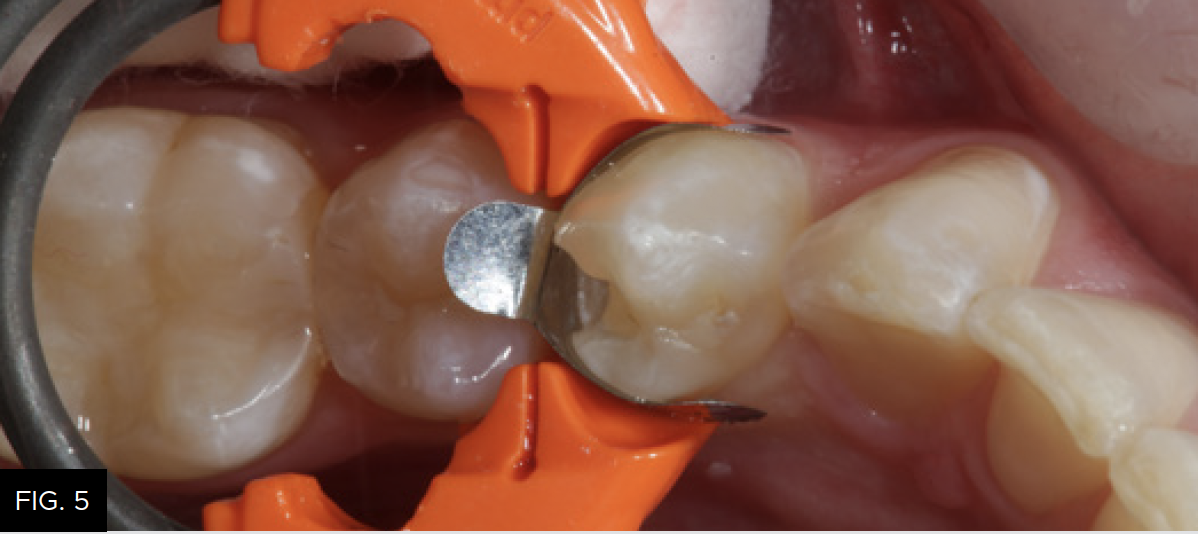

Because of the concave anatomic shape when applied, the proximal contact will be located approximately one millimeter apical to the height of the marginal ridge. Next, the gingival portion of the band is stabilized and sealed against the cavosurface margin of the preparation using the appropriate size DualForce Active-Wedge (Clinician’s Choice). The size of the wedge should be wide enough to hold the gingival portion of the matrix band sealed against the cavosurface of the preparation, while the opposite side of the wedge sits firmly against the adjacent tooth surface. Once the DualForce matrix is properly wedged and ring placed, the restorative process for tooth number 21 (34) can be started. (FIG. 5)

The sectional matrix (DualForce, Clinician’s Choice) is shown in place on tooth number 21 (34). Note the precise gingival seal due to the DualForce Active-Wedge and the accuracy of the adaptation of the matrix to the vertical walls of the preparation that will help eliminate flash and excess after composite placement.